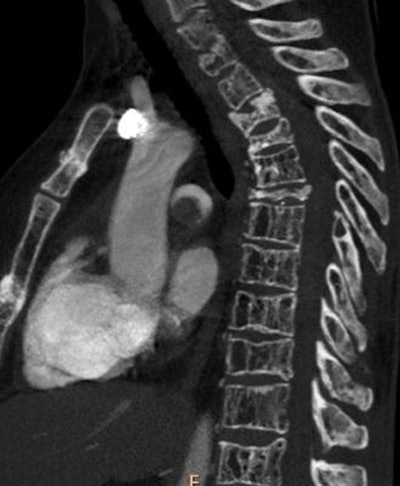

| Sagittal image shows a massive filling defect in the pulmonary trunk. Multiple vertebral and sternal fractures are also depicted. |

The results showed PE in 73 (30.5%) of 239 patients; of these cases, 45 (61.6%) were categorized as massive and 28 (38.4%) as nonmassive.

PE was categorized as massive (affecting the main trunk) or nonmassive (segmental or subsegmental emboli), and the study team logged the prevalence of other chest findings such as pulmonary consolidation, pleural effusion and atelectasis, and tumors, primary or secondary. A venous scan of the abdomen and pelvis was added to look for DVT, and correlation between D-dimer levels and PE was calculated.